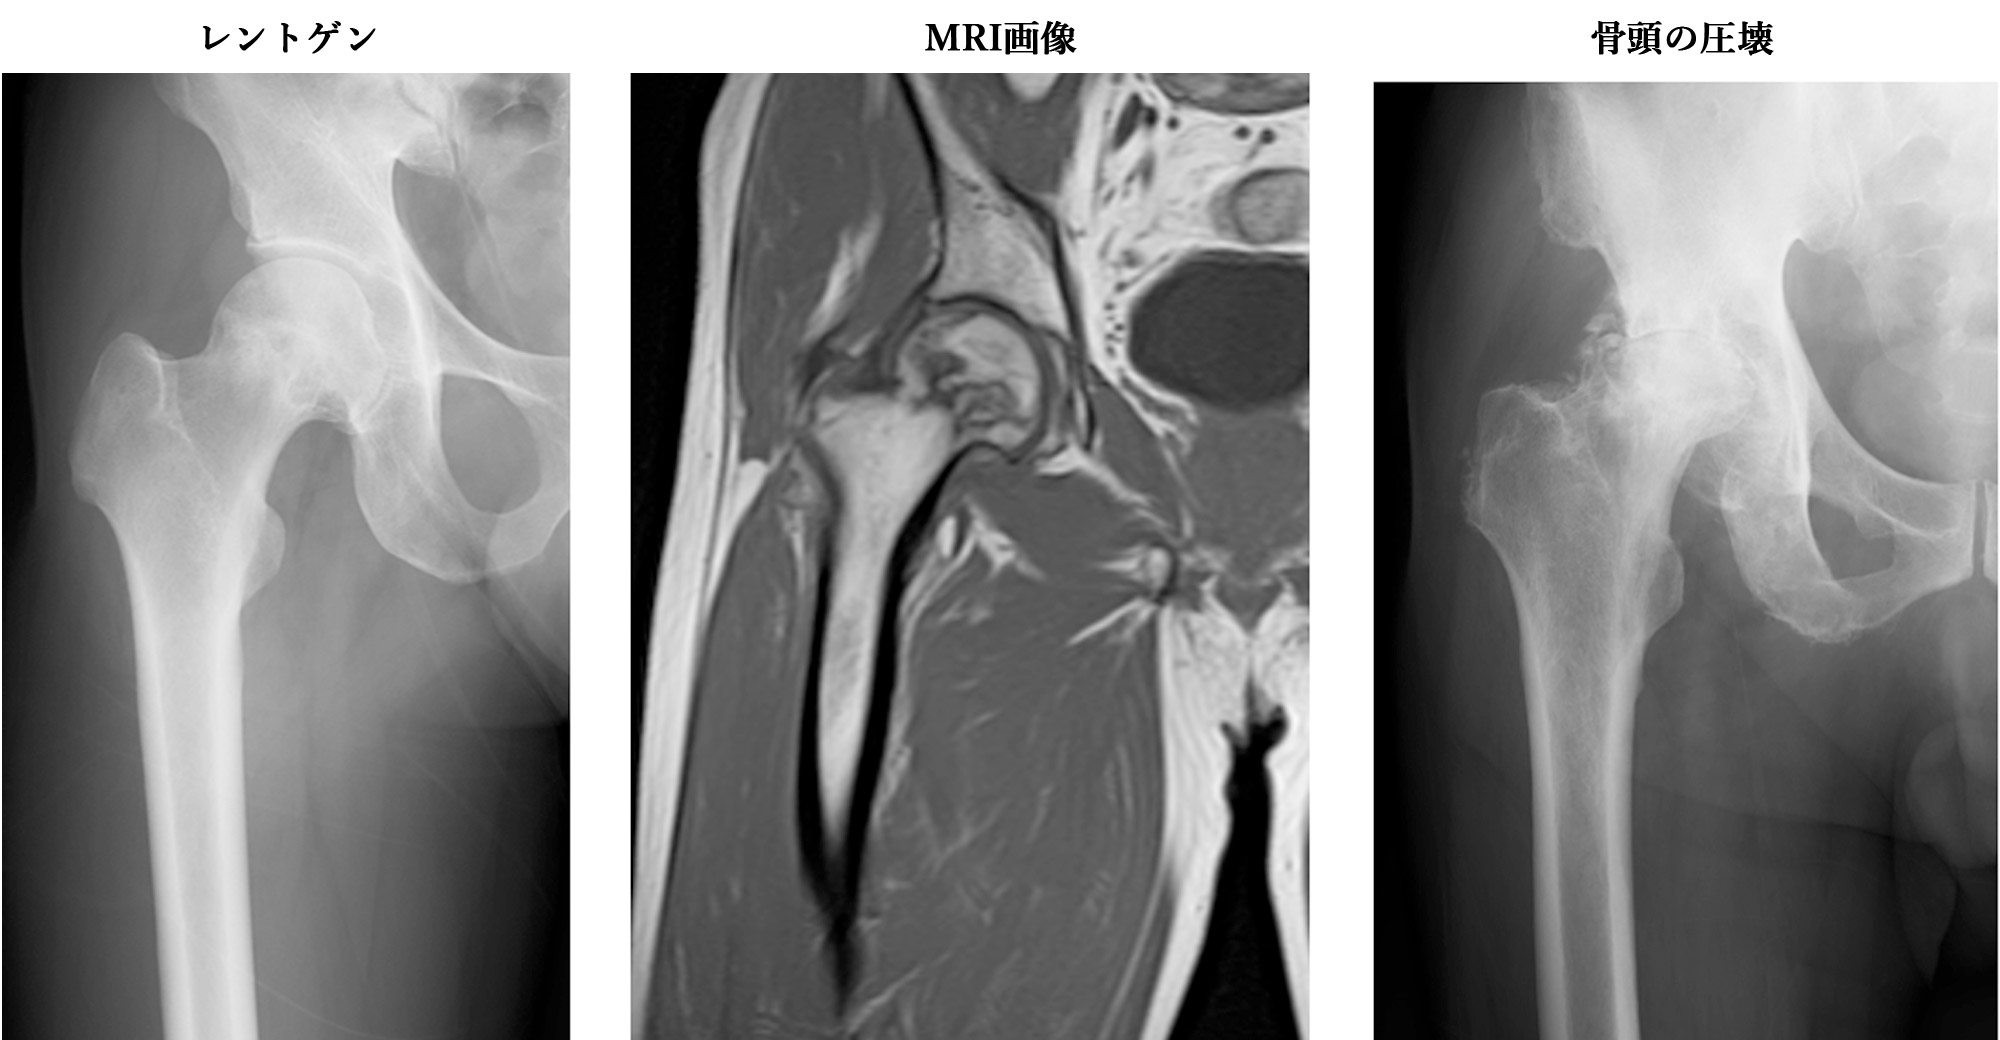

ふとももの骨を大腿骨と言います。脚の付け根にある大腿骨の球状の部分(骨頭)が何らかの原因で壊死してしまう病気です。多量の飲酒や喫煙、他の病気でステロイド剤での治療を受けたことのある場合に発症することが多いと言われていますが、はっきりとした原因は解明されていません。骨頭が壊死して関節面が陥没、圧壊すると激しい痛みが出現し、歩行困難となります。大腿骨頚部骨折や外傷性股関節脱臼後に大腿骨頭壊死症に移行する場合もあります。

レントゲン、CT、MRI検査、骨シンチグラム